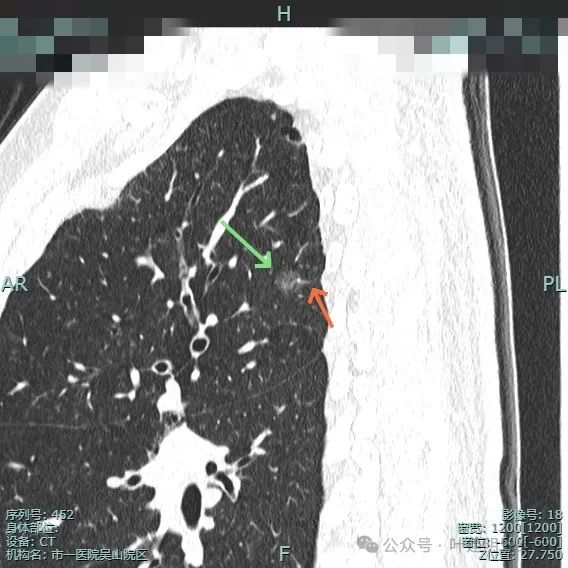

先来看两肺多发结节的总体情况:

病灶1:左上叶肺尖淡磨玻璃影,轮廓稍显模糊,少许慢性炎或肺泡间隔增宽可能性大。

病灶2:右上肺胸膜下微小磨玻璃结节,表面欠光滑,倾向肺泡上皮增生之类的病变,目前不十分确切,但风险总是低的。